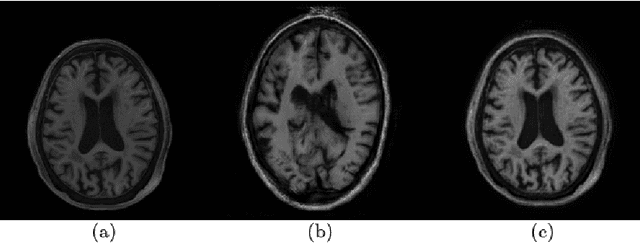

Automatic segmentation of white matter hyperintensities in magnetic resonance images is of paramount clinical and research importance. Quantification of these lesions serve as a predictor for risk of stroke, dementia and mortality. During the last years, convolutional neural networks (CNN) specifically tailored for biomedical image segmentation have outperformed all previous techniques in this task. However, they are extremely data-dependent, and maintain a good performance only when data distribution between training and test datasets remains unchanged. When such distribution changes but we still aim at performing the same task, we incur in a domain adaptation problem (e.g. using a different MR machine or different acquisition parameters for training and test data). In this work, we explore the use of cycle-consistent adversarial networks (CycleGAN) to perform unsupervised domain adaptation on multicenter MR images with brain lesions. We aim at learning a mapping function to transform volumetric MR images between domains, which are characterized by different medical centers and MR machines with varying brand, model and configuration parameters. Our experiments show that CycleGAN allows us to reduce the Jensen-Shannon divergence between MR domains, enabling automatic segmentation with CNN models on domains where no labeled data was available.